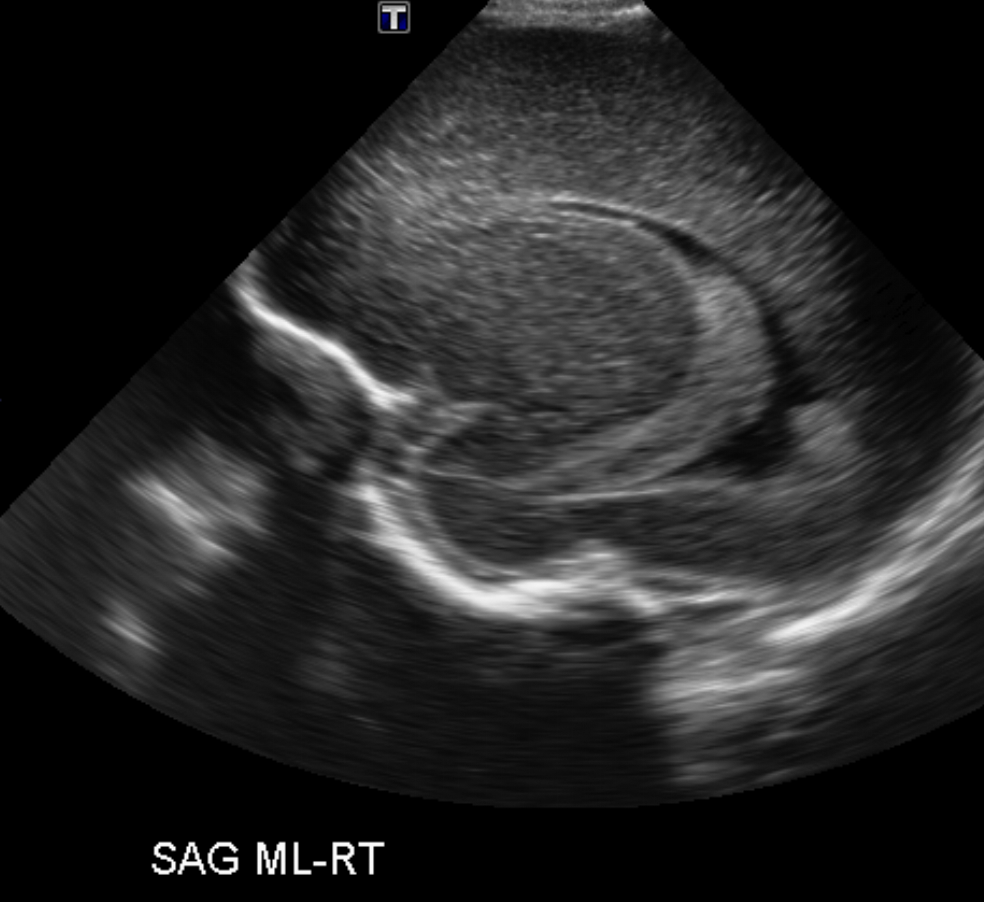

Section 1 Submit Findings Case151 Findings Brain The brain is immature. Yes No There is under-sulcation and open sylvian fissures. Yes No There is/are multiple hypoechoic areas in the periventricular white matter. Yes No There is/are multiple hyperechoic areas in the periventricular white matter. Yes No There is diffuse cerebral edema with diffusely increased echogenicity of the brain parenchyma and loss of grey white matter differentiation. Yes No The thalami/basal ganglia are hypoechoic. Yes No There is periventricular calcification. Yes No There is intra-parenchymal calcification. Yes No CSF spaces/ventricular system There is a prominence of the extra axial fluid spaces. Yes No There are debris/septations in the extra axial fluid spaces. Yes No There are debris/septations in the ventricles. Yes No There is a subdural collection on the right/left side. Yes No There is prominence of the ventricular system. Yes No There is an asymmetry of the ventricular system. Yes No There is a cavum septum pellucidum. Yes No There is a midline shift towards right/left. Yes No The choroid plexus is bulky/lobulated. Yes No There is a choroid plexus cyst measuring… Yes No There are debris/clots in the occipital horn. Yes No There is a posterior fossa cyst measuring… Yes No The tentorium is elevated/depressed. Yes No The lateral ventricle/s are dilated. Yes No The third ventricle is dilated. Yes No The 4th ventricle is dilated. Yes No There are pseudo cysts. Yes No Germinal matrix hemorrhage (Only in the premature infants): Please do not answer if the patient is a full term. There is a germinal matrix hemorrhage, consistent with a grade I hemorrhage. Yes No There is an intraventricular extension consistent with a grade II hemorrhage. Yes No There is an intraventricular extension with the dilatation of ventricles, consistent with a grade III hemorrhage. Yes No There is an intra-parenchymal extension, consistent with grade IV hemorrhage. Yes No On color Doppler examination, the Resistive index in the anterior cerebral artery is… There is a loss of the diastolic flow on the Doppler exam. Yes No There is altered vascularity on Doppler imaging. Yes No There is an AVM in the region of… Yes No